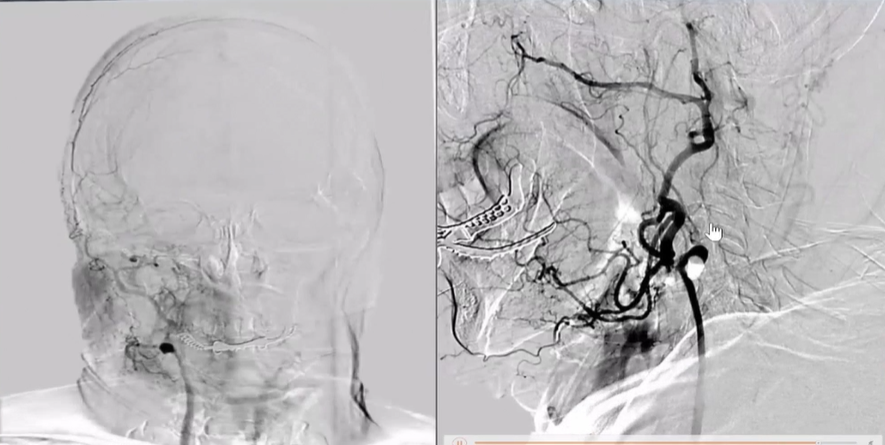

术前右侧椎动脉造影

病历夹什么径技·第152期|串联营病历夹:川陕大营_https://www.jmylbn.com_新闻资讯_第11张

病历夹什么径技·第152期|串联营病历夹:川陕大营_https://www.jmylbn.com_新闻资讯_第12张

病历夹什么径技·第152期|串联营病历夹:川陕大营_https://www.jmylbn.com_新闻资讯_第13张<<滑动查看下一张图片>>

术前左侧椎动脉造影

病历夹什么径技·第152期|串联营病历夹:川陕大营_https://www.jmylbn.com_新闻资讯_第14张

病历夹什么径技·第152期|串联营病历夹:川陕大营_https://www.jmylbn.com_新闻资讯_第15张

病历夹什么径技·第152期|串联营病历夹:川陕大营_https://www.jmylbn.com_新闻资讯_第16张

<<滑动查看下一张图片>>

左侧颈总动脉造影

病历夹什么径技·第152期|串联营病历夹:川陕大营_https://www.jmylbn.com_新闻资讯_第17张

右侧颈总动脉造影

病历夹什么径技·第152期|串联营病历夹:川陕大营_https://www.jmylbn.com_新闻资讯_第18张

病历夹什么径技·第152期|串联营病历夹:川陕大营_https://www.jmylbn.com_新闻资讯_第19张

病历夹什么径技·第152期|串联营病历夹:川陕大营_https://www.jmylbn.com_新闻资讯_第20张